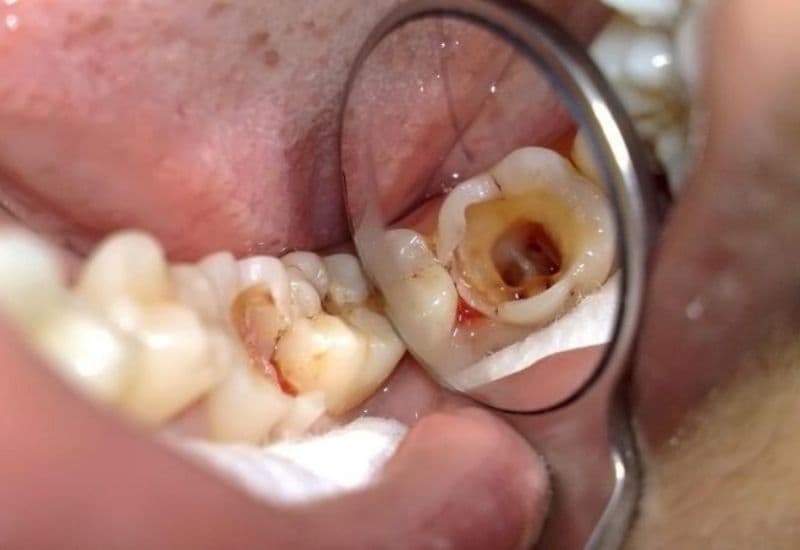

2.2. Răng có những vết đen hoặc xuất hiện lỗ li ti

Sâu răng ban đầu thường biểu hiện bằng các đốm trắng mờ, sau đó chuyển sang màu nâu hoặc đen. Một số trẻ còn xuất hiện lỗ nhỏ trên bề mặt răng hàm – đây là dấu hiệu men răng đã bị phá hủy, cần đưa trẻ đi khám nha sĩ ngay để tránh tình trạng sâu răng tiến triển.

– Sâu răng nặng: Lúc này, vi khuẩn đã xâm nhập vào tủy răng, gây đau nhức dữ dội. Bác sĩ có thể chỉ định điều trị tủy răng sữa, giúp loại bỏ phần tủy bị viêm và giữ lại chân răng để răng vẫn duy trì chức năng. Nếu răng bị hư hỏng quá nặng, không thể bảo tồn, trẻ có thể cần nhổ răng. Sau nhổ, bác sĩ sẽ tư vấn giải pháp phục hình phù hợp để đảm bảo răng vĩnh viễn mọc đúng vị trí sau này.